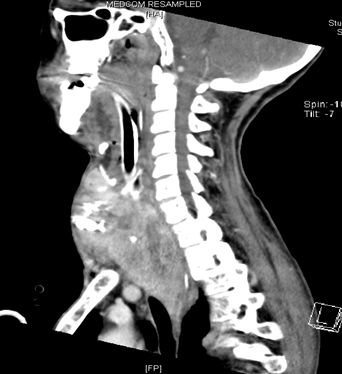

困难气道患者拔管流程见图6。

图6 困难气道患者拔管流程